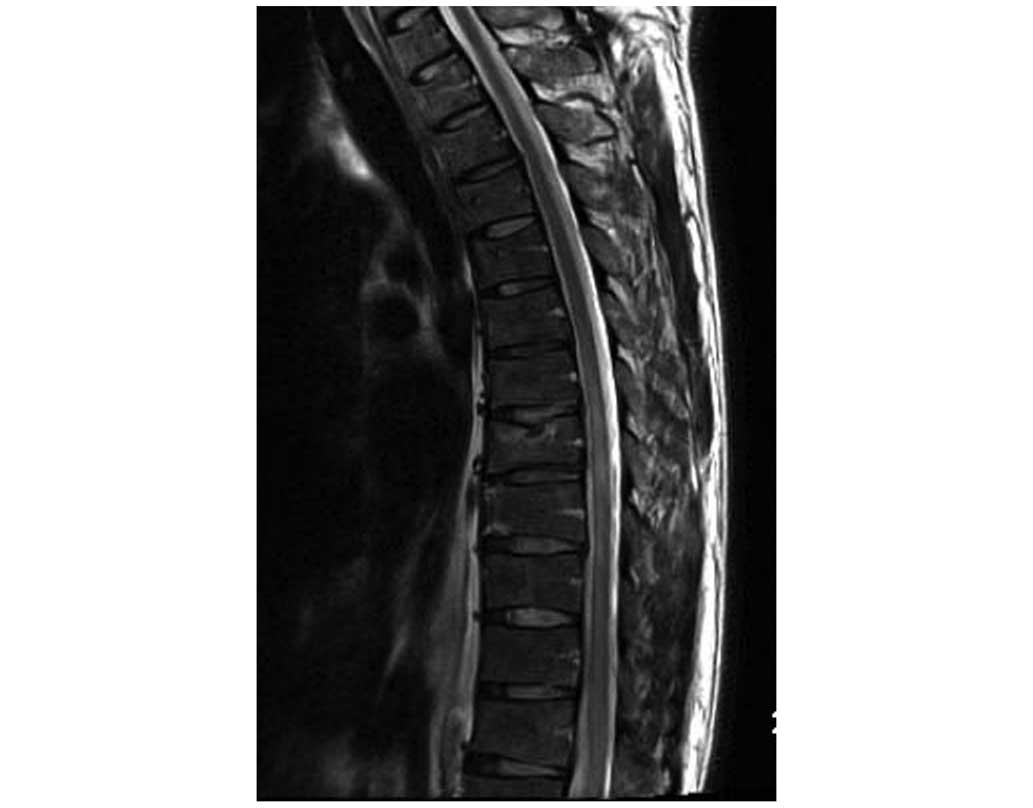

The present study reports the case of an adult patient with non-traumatic acute paraplegia following a computed tomography (CT)-guided automated cutting needle biopsy (ACNB). Multiple nodules and masses were revealed on performing chest radiography and CT on a 45‑year‑old man. In order to make a pathological diagnosis, a CT‑guided biopsy using an automatic cutting needle was performed. However, 10 min after the biopsy, a weakness of the lower extremities occurred, and the patient collapsed to the ground, albeit with clear consciousness. Spinal magnetic resonance imaging (MRI) performed subsequently revealed no abnormal findings in the spinal cord. An MRI performed 24 h later, however, revealed swelling of the thoracic spinal cord and a high‑signal‑intensity lesion in T2‑weighted images at the level of T7, T8 and T9. The patient subsequently received hyperbaric oxygen therapy for a few days, and rehabilitative treatment over the course of a few weeks. At 6 months following the biopsy, the patient was unable to walk, although the patient could stand for 10 min and defecate independently. Currently, the patient remains active in daily life, in spite of confinement to a wheelchair. The present case study was reported to raise the awareness of the possibility of spinal cord ischemia and acute paraplegia following a CT‑guided ACNB of the lungs. The mechanism underlying spinal cord ischemia remains to be fully elucidated, although is thought to be multifactorial, involving air embolism.

Figure 1

Figure 2